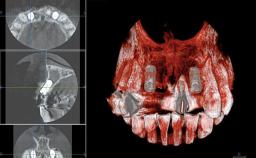

Replacement of Two Central Incisors and One Lateral Incisor with a Fixed Dental Prosthesis on Two Bone-Level Implants

A 38-year-old woman presented with an esthetically unacceptable fixed partial denture replacing teeth 11, 21, 22. She had lost these teeth due to trauma when she was a child. The patient was not in pain but very concerned based on her previous experience that dental treatments had never satisfied her esthetic expectations. She was in good general health and reported no regular medications. No periodontal disease was noted despite the fact that the buccal flange of the prosthesis impeded cleaning of the tooth abutments. The patient did not smoke and complied with home maintenance requirements, as evidenced by her good oral hygiene status.